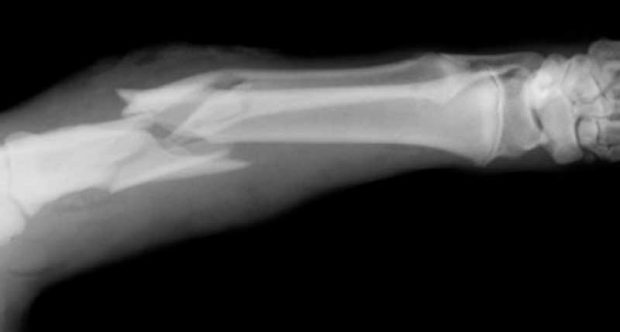

درمان شکستگی استخوان با روشی جالب و سریع دز حالی توسط محققان امکان پذیر شده شده است که آن ها با استفاده از سلول های بنیادین مایع کیسه آب مادر ، موش هایی با استخوان های شکننده را درمان کردند. این نوع درمان به ۷۹ درصد کاهش شکستگی در استخوان های حیوان منجر شد و حتی آن ها را قوی تر کرد. در ادامه با میهن پست همراه شوید.

گیلو و همکارانش برای درمان شکستگی استخوان ، سلول های بنیادنی مایع کیسه آب مادر – مایع آمنیوتیک – را خارج کرده و به موش هایی تزریق کردند که استخوان های ضعیفی داشتند. هشت هفته پس از تزریق سلول های بنیادین موارد مربوط به شکستگی استخوان های پا در موشها کاهش یافته بود.